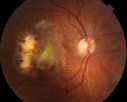

Bilateral new wet AMD with subretinal hemorrhage

amd_heme_jste_071415_31.jpg

23 files, last one added on Sep 22, 2015

Album viewed 683 times